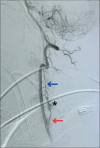

Figure 2:

Lateral view of left vertebral artery angiogram. The study revealed an arteriovenous shunt (black asterisk) inside the cervical canal, fed by the left C6 radicular artery (red arrow) and with retrograde venous drainage through the anterior cervical venous plexus (blue arrow).